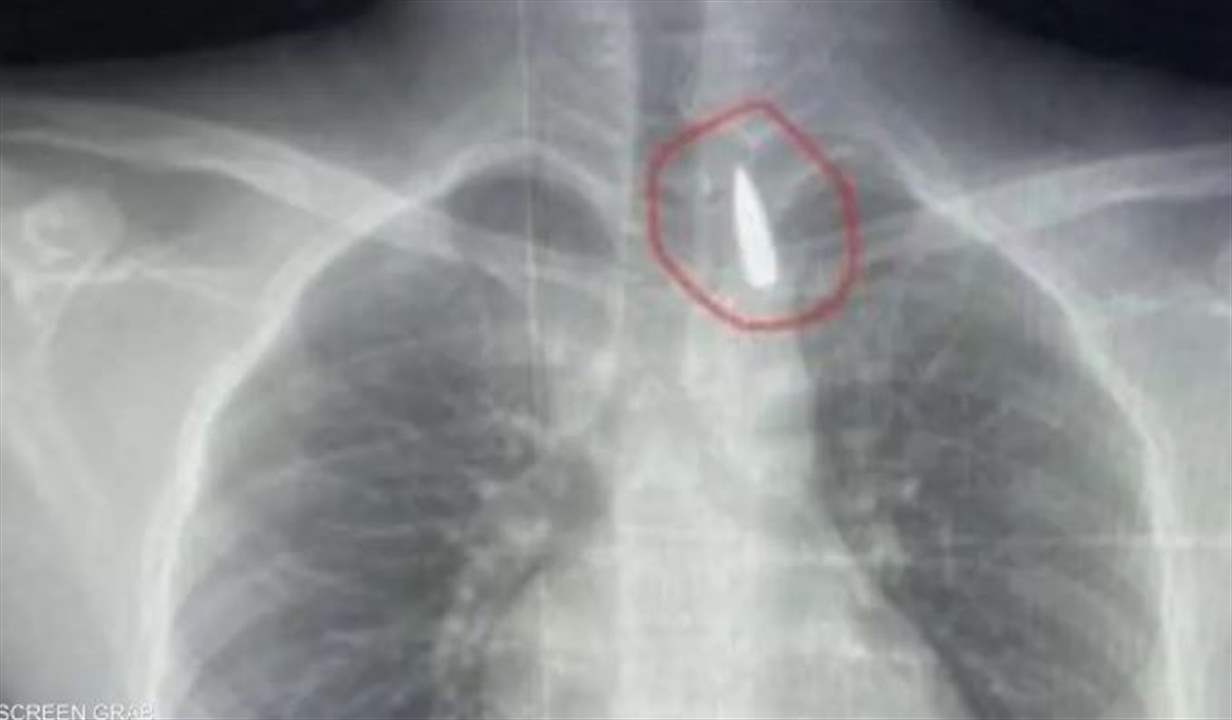

جراحة معقدة.. إنقاذ حياة طفل من غزة مصاب بمقذوف في صدره

في جراحة نادرة ومعقدة.. أطباء مصريون بمشفى جامعة الإسكندرية يتمكنون ...